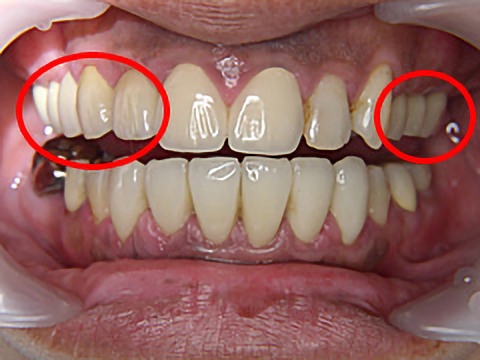

症例3

年齢 | 42歳 |

---|---|

性別 | 女性 |

費用 | 1本あたり330,000円+保険で必要な金額(抜歯など) |

治療期間/治療回数 | 1年半/20回 |

治療におけるリスク |

骨の状態により治療ができない場合があります。 一度埋め込んだインプラントが脱離する可能性があります。 上部構造は消耗品です。一生持つものではなく、破折する可能性があります。 |

歯科治療が怖くて長きにわたりお口を放置されていましたが、一大決心の後、当院にて治療を受けられました。

右上4本、左上も3本、抜歯即時埋入を含めてインプラント治療を受け、噛み合わせを取り戻すことができました。また、下顎の前歯も大きくすり減っていたため、オールセラミックスで治療しました。